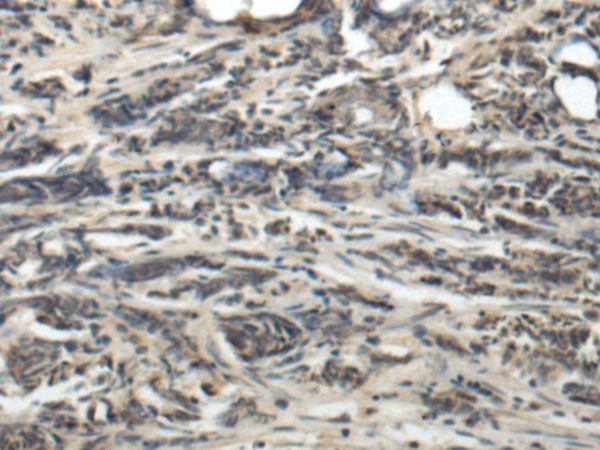

分类: 科研抗体货号: P07363别名: AILIM; CD278; CVID1应用: IHC反应种属: Human